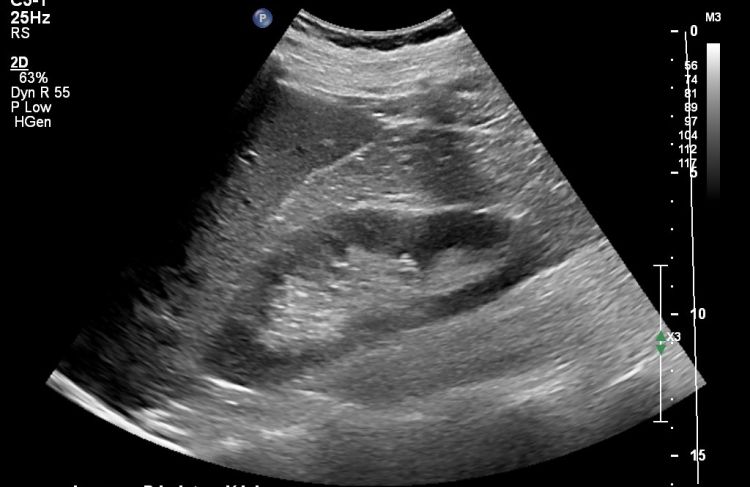

Adult Abdomen

Adult Abdomen is a course offered through Advanced Training for Sonographers. This online course with optional hands-on skills day is designed to support a sonographer’s abdominal knowledge and help prepare for the ARDMS AB examination. Learn more and register for Adult Abdomen.